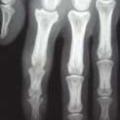

Le tableau clinique typique est constitué, chez une personne atteinte de psoriasis, par la survenue de douleurs articulaires d’horaire inflammatoire, révélant des arthrites périphériques, de forme oligoarticulaires et asymétriques le plus souvent, et pouvant atteindre les articulations interphalangiennes distales (fig. 1 et 2). Les manifestations cutanées du RP comprennent le psoriasis (généralement psoriasis en plaques) et le psoriasis unguéal, souvent marqué par un épaississement de l’ongle ressemblant à une mycose.

Dans les formes oligoarticulaires, on peut traiter avec un traitement symptomatique seul. Cependant, chez les patients atteints de forme polyarticulaire (plus de quatre synovites) ou présentant une maladie mono- ou oligo-articulaire mais avec des facteurs de mauvais pronostic (atteinte structurale à la radiographie, syndrome inflammatoire biologique, présence de dactylite ou d’atteinte des ongles), il est recommandé de commencer directement ou très rapidement un traitement de fond.6,7